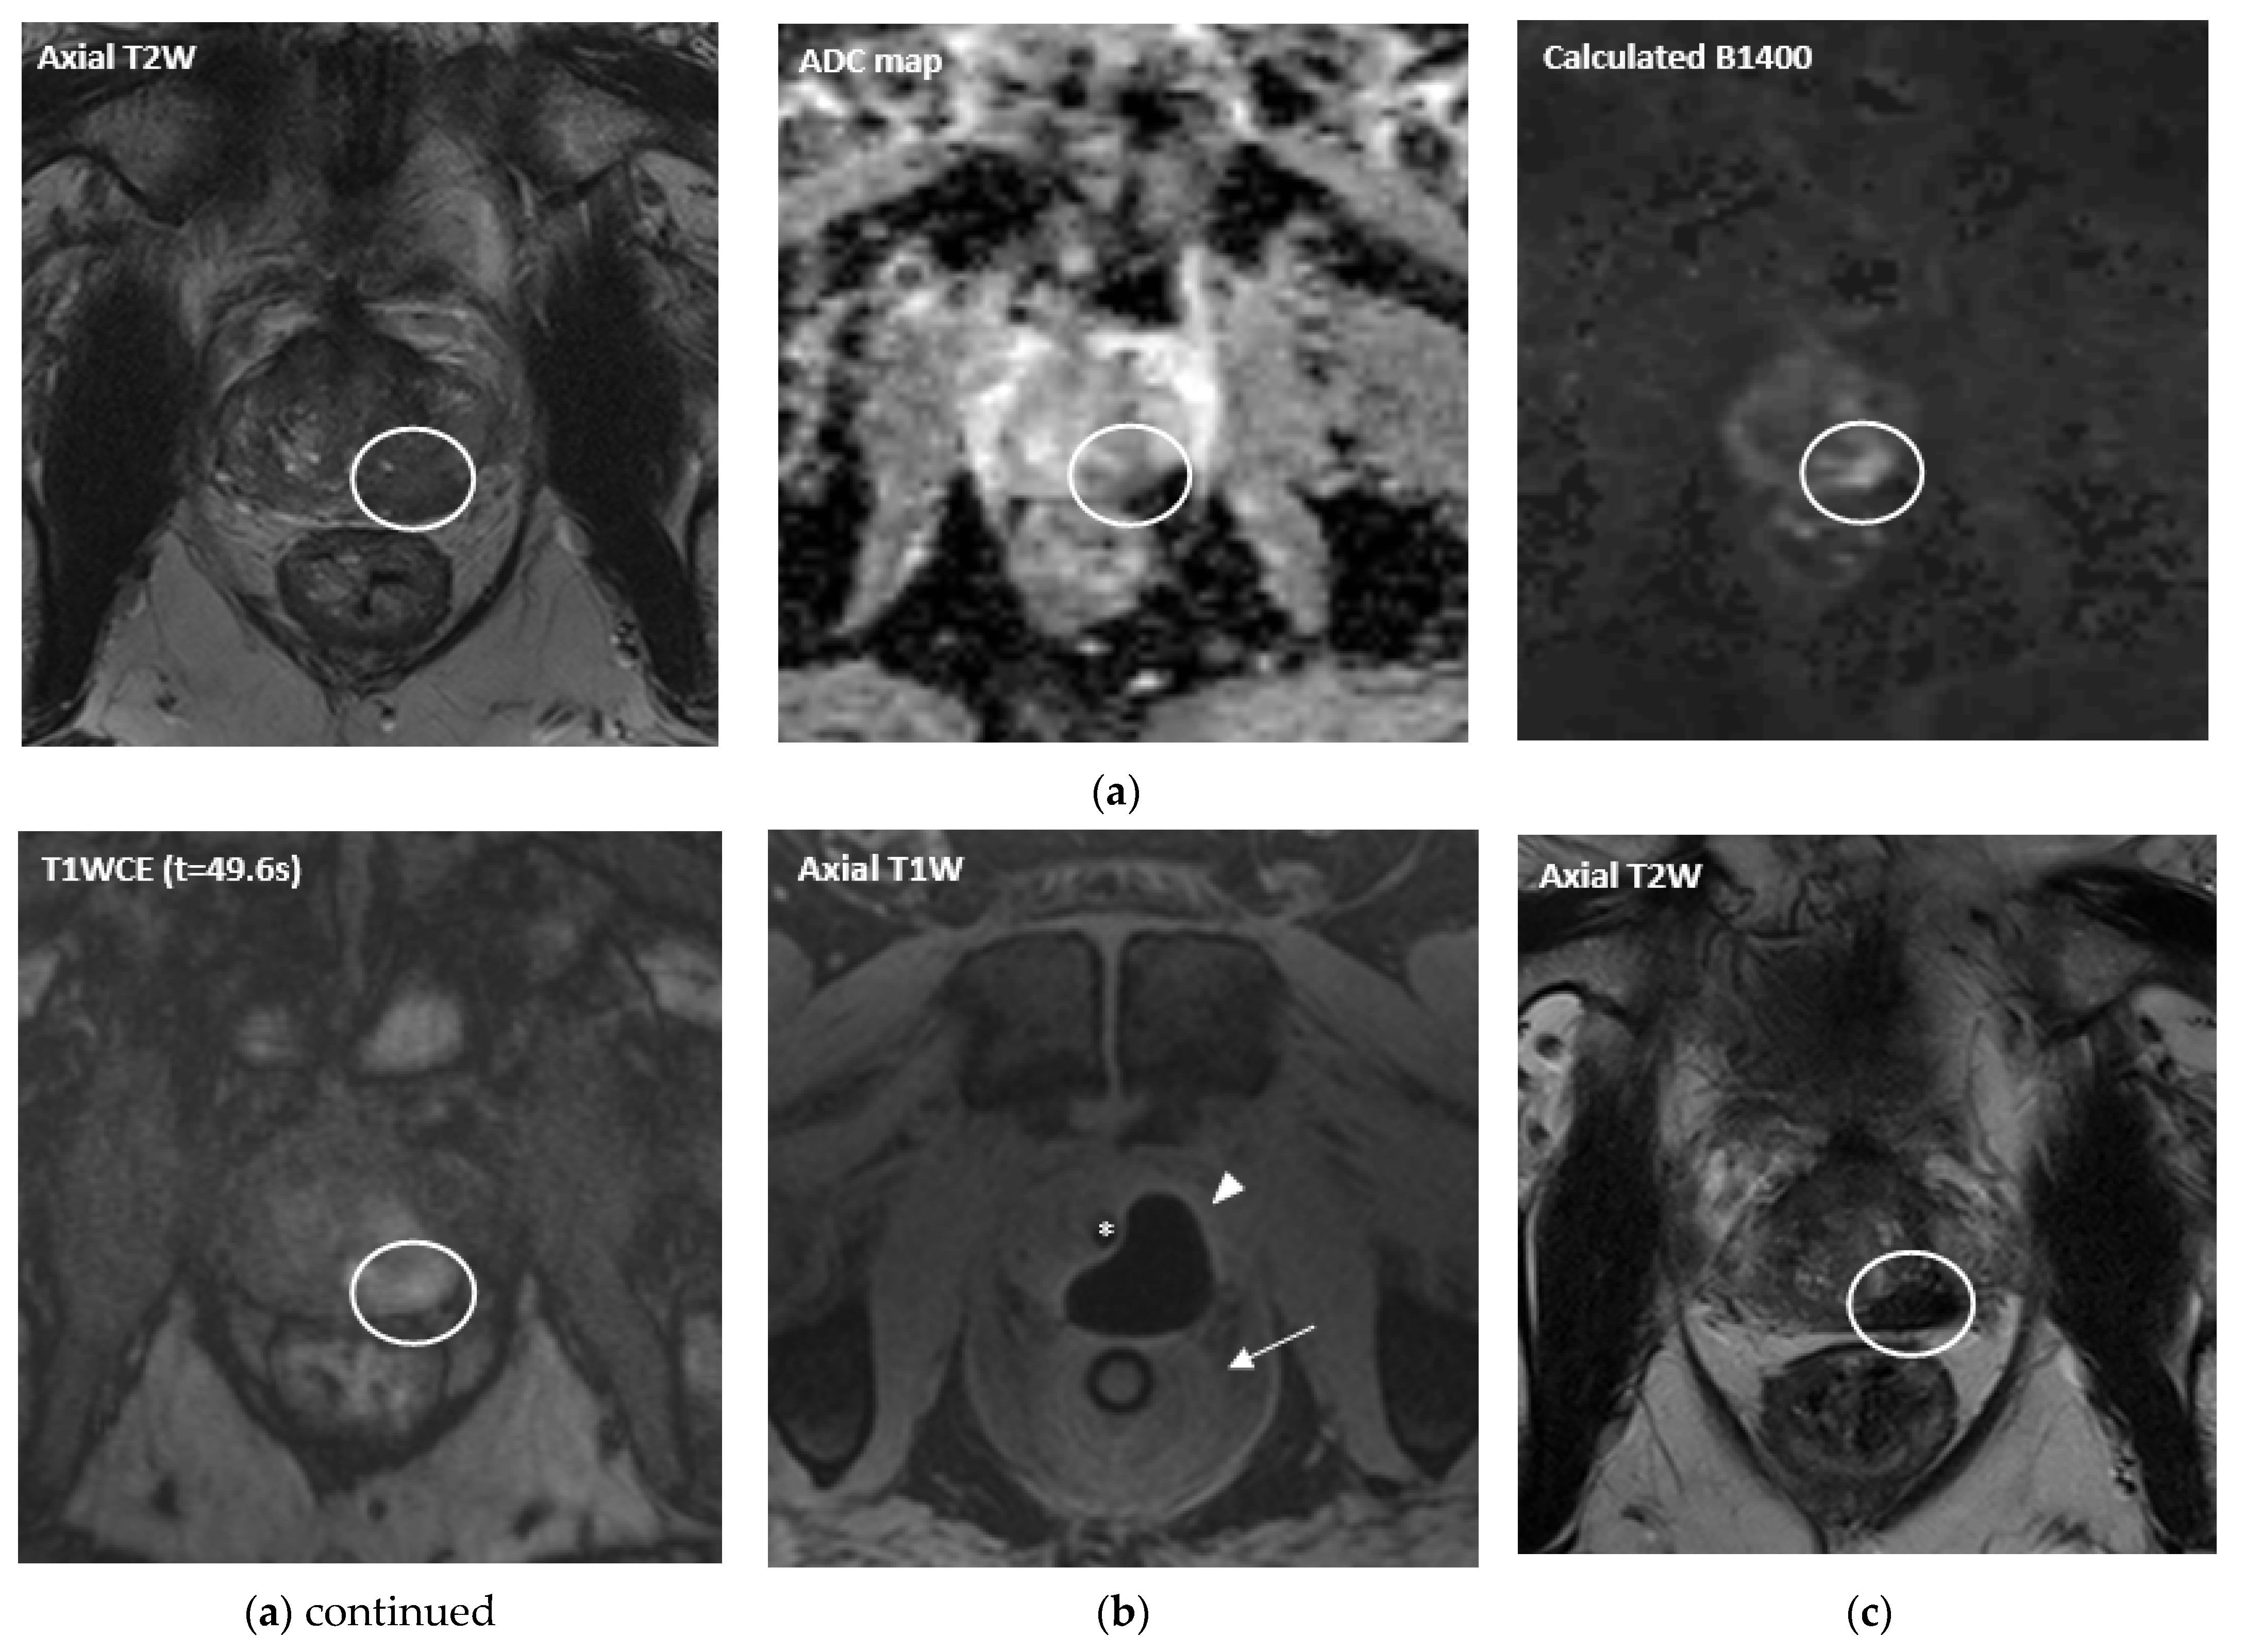

- Bomers, J.G.R.; Cornel, E.B.; Fütterer, J.J.; Jenniskens, S.F.M.; Schaafsma, H.E.; Barentsz, J.O.; Sedelaar, J.P.M.; De Kaa, C.A.H.-V.; Witjes, J.A. MRI-guided focal laser ablation for prostate cancer followed by radical prostatectomy: Correlation of treatment effects with imaging. World J. Urol. 2016, 35, 703–711. [Google Scholar] [CrossRef] [PubMed]

- Oto, A.; Sethi, I.; Karczmar, G.; McNichols, R.; Ivancevic, M.K.; Stadler, W.M.; Watson, S.; Eggener, S. MR Imaging–guided Focal Laser Ablation for Prostate Cancer: Phase I Trial. Radiology 2013, 267, 932–940. [Google Scholar] [CrossRef]

- Natarajan, S.; Raman, S.; Priester, A.M.; Garritano, J.; Margolis, D.J.; Lieu, P.; Macairan, M.L.; Huang, J.; Grundfest, W.; Marks, L.S. Focal Laser Ablation of Prostate Cancer: Phase I Clinical Trial. J. Urol. 2015, 196, 68–75. [Google Scholar] [CrossRef]

- Mehralivand, S.; George, A.K.; Hoang, A.N.; Rais-Bahrami, S.; Rastinehad, A.R.; Lebastchi, A.H.; Ahdoot, M.; Siddiqui, M.M.; Bloom, J.; Sidana, A.; et al. MRI-guided focal laser ablation of prostate cancer: A prospective single-arm, single-center trial with 3 years of follow-up. Diagn. Interv. Radiol. 2021, 27, 394–400. [Google Scholar] [CrossRef]

- Eggener, S.E.; Yousuf, A.; Watson, S.; Wang, S.; Oto, A. Phase II Evaluation of Magnetic Resonance Imaging Guided Focal Laser Ablation of Prostate Cancer. J. Urol. 2016, 196, 1670–1675. [Google Scholar] [CrossRef]

- Lepor, H.; Llukani, E.; Sperling, D.; Fütterer, J.J. Complications, Recovery, and Early Functional Outcomes and Oncologic Control Following In-bore Focal Laser Ablation of Prostate Cancer. Eur. Urol. 2015, 68, 924–926. [Google Scholar] [CrossRef]

- Chao, B.; Lepor, H. 5-Year Outcomes Following Focal Laser Ablation of Prostate Cancer. Urology 2021, 155, 124–129. [Google Scholar] [CrossRef]

- Walser, E.; Nance, A.; Ynalvez, L.; Yong, S.; Aoughsten, J.S.; Eyzaguirre, E.J.; Williams, S.B. Focal Laser Ablation of Prostate Cancer: Results in 120 Patients with Low- to Intermediate-Risk Disease. J. Vasc. Interv. Radiol. 2019, 30, 401–409.e2. [Google Scholar] [CrossRef] [PubMed]